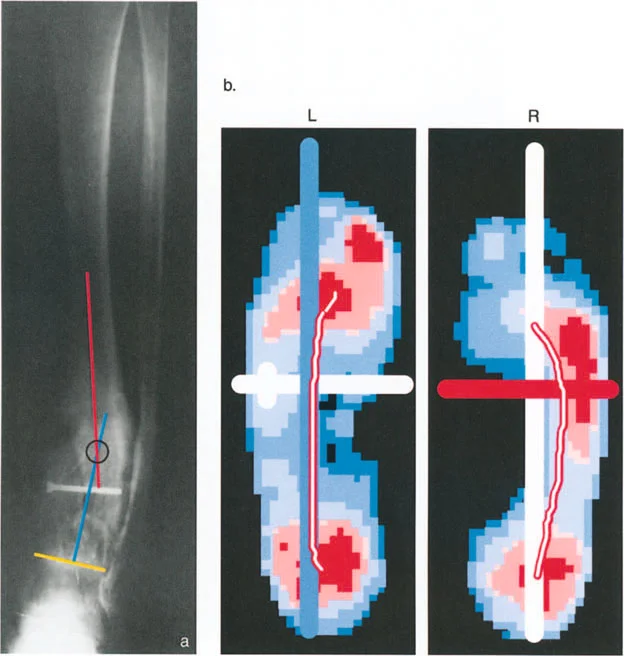

3. تحميل المفصل غير الطبيعي ومتجه رد فعل الأرض (GRV)

متجه رد فعل الأرض (Ground Reaction Vector - GRV) هو القوة المحصلة التي تؤثر بها الأرض على القدم عند نقل وزن الجسم أثناء الوقوف. يتم تحديدها بواسطة قانون نيوتن الثالث. في طرف سفلي متوافق تمامًا، يمر متجه رد فعل الأرض مباشرة عبر مركز مفاصل الورك والركبة والكاحل في كل من المستويين الأمامي والسهمي. وهذا يضمن توزيعًا متساويًا وفسيولوجيًا لقوى الضغط عبر الغضروف المفصلي.

تزيح تشوهات العظام متجه رد فعل الأرض بعيدًا عن مركز المفصل، مما يخلق عزم دوران مرضيًا.

أمراض المستوى الأمامي (التقوس/الفحج - Varus/Valgus):

إذا كان المريض يعاني من تشوه تقوس (Varus) في عظم الساق أو الفخذ، فإن متجه رد فعل الأرض يتحرك نحو الداخل (إنسيًا). كلما مر متجه رد فعل الأرض أكثر إنسيًا بالنسبة لمركز الركبة، زاد عزم دوران التقريب. وهذا يزيد بشكل كبير من قوى الضغط على الجزء الإنسي من سطح عظم الساق القريب (medial tibial plateau).

بينما يحمل الوقوف على ساق واحدة طبيعيًا الجزء الإنسي بحوالي 75%، فإن تشوه التقوس الشديد (الذي يسبب انحرافًا كبيرًا في المحور الميكانيكي، أو MAD) يمكن أن ينقل 100% من الحمل إلى الجزء الإنسي. على مدى فترات طويلة، يؤدي هذا التحميل الميكانيكي الموضعي المفرط إلى تدهور سريع وتدريجي للغضروف المفصلي، وتصلب تحت الغضروف، وتكون نتوءات عظمية، وفي النهاية إلى التهاب مفصل الركبة في مراحله المتأخرة.

سوء المحاذاة في المستوى الأمامي: مجمع القدم والكاحل

تُقدم تشوهات المستوى الأمامي (التقوس والفحج) تحديات فريدة لأن التعويض يعتمد بشكل كبير على المفصل تحت الكاحل (subtalar joint) المعقد ومتعدد المحاور. يُعتبر المفصل تحت الكاحل المعوض الكبير للطرف السفلي.

تقوس وفحج الجزء البعيد من عظم الساق